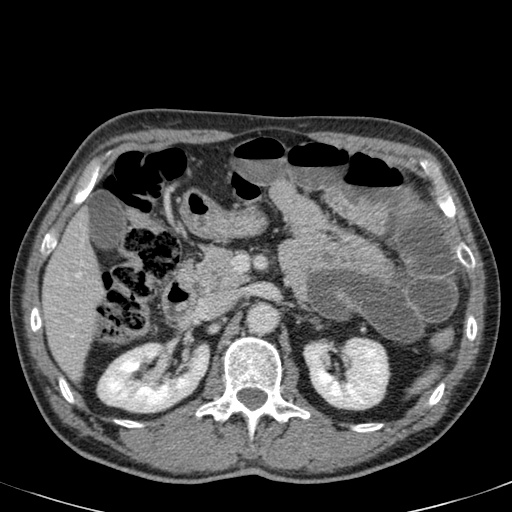

Ca lâm sàng bên trái cho thấy một bệnh nhân khác bị tắc ruột dạng quai kín.

Mặc dù các mạch máu ngấm thuốc tốt, nhưng dường như thành ruột không ngấm thuốc.

Các dấu hiệu thiếu máu cục bộ khác trong ca này bao gồm phù nề mạc treo và dày thành ruột.

Ruột bị nhồi máu được phát hiện trong quá trình phẫu thuật.

Nếu quai kín dài hơn và định hướng vuông góc với mặt phẳng cắt, chúng ta sẽ thấy một cụm quai ruột như trong ca lâm sàng bên trái.

Đôi khi điều này khó nhận biết chỉ trên các lát cắt ngang và các tái tạo mặt phẳng coronal hoặc sagittal có thể hữu ích.

Trong ca này, cũng có phù nề mạc treo và cổ